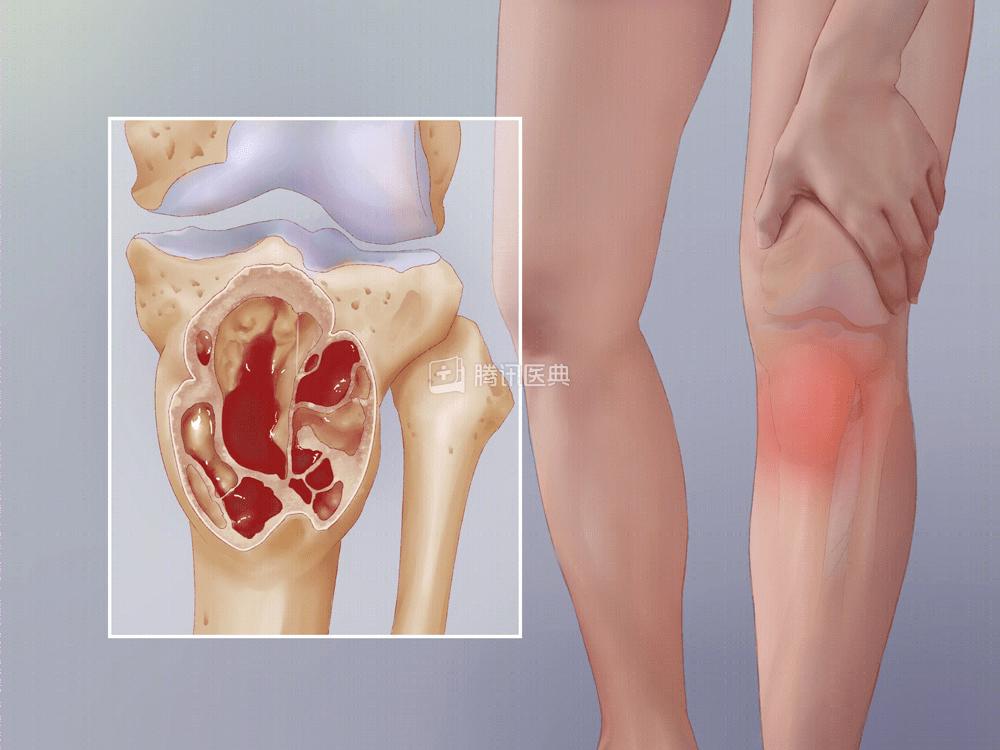

13岁以下的孩子,有时双腿会出现痉挛性的肌肉痛,通常在午后或晚上出现,甚至能让孩子在半夜痛醒。生长痛一般开始于3~4岁,往往会在孩子8~12岁时复发[3]。

(生长痛示意图。医典自制)那生长痛和骨肿瘤怎么区别呢?

一个最简单的方法就是:看孩子一条腿不舒服,还是两条腿都疼。

生长痛一般会出现在双腿,特别是在大腿前部、小腿后部或膝盖后部。

如果只有一条腿出现疼痛,那可能是更严重疾病的征兆。